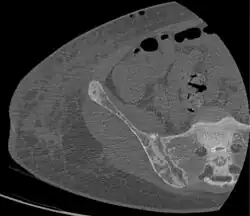

CT shows focal areas of osteosclerosis.[18] -

Brown tumors in the pelvis and a hip fracture.[18] -

CT scan of the same case.[18]